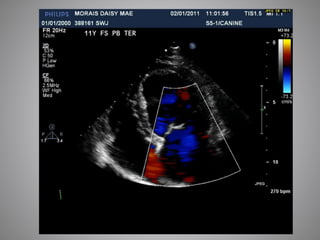

• #31 MMVD: Echocardiography is not essential is diagnosing CHF due to MMVD but it remains useful for confirming the severity of cardiac enlargement (esp in the shallow chested dogs with rads that are difficult to interpret) Look for PHT Chordal rupture LA tear DCM – echo is essential for dx as this disease offers a worse prognosis than MMVD HCM - echo is usually required for diagnosis, staging severity, looking for thrombus formation and for diagnosis of end stage disease that may warrant additional therapy. This video loop is a left parasternal oblique view of the left atrium and auricle showing severe spontaneous echo contrast and a thrombus in the left auricle